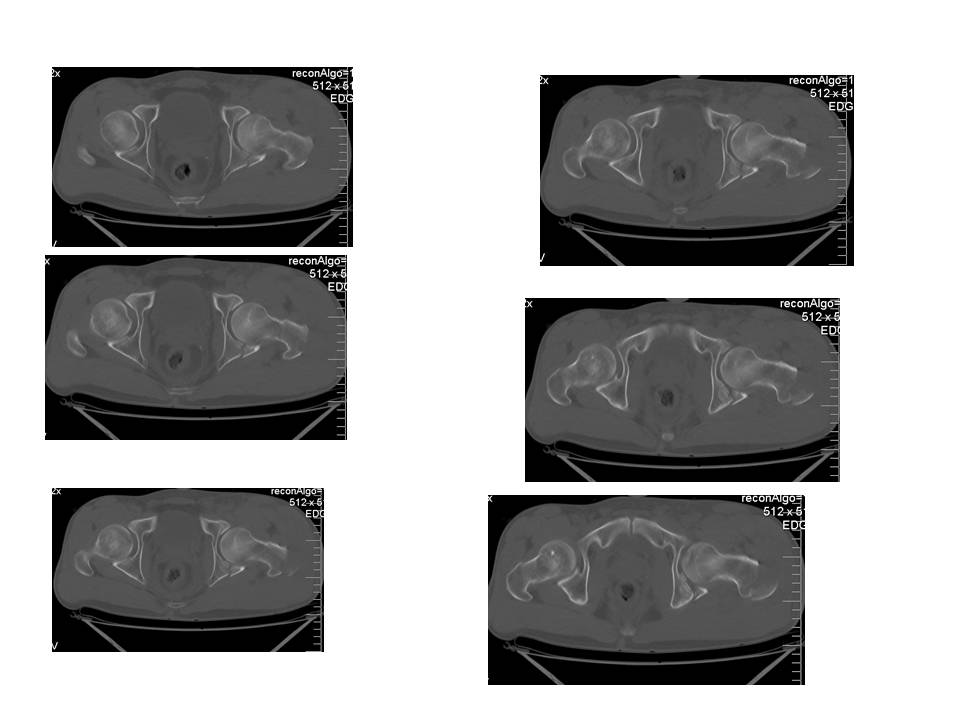

Больной 24 лет, травму получил катаясь на горных лыжах.

На рентгенограммах вертельный перелом. Но при детальном изучении

снимков появилось подозрение на перелом головки бедра. Это побудило

выполнить КТ.

На КТ перелом заднего края вертлужной впадины.

Планируем проксимальный стержень. А вот с вертлужной впадиной вопрос.

Синтезировать или консервативно.

"За операцию" внутрисуставной перелом, с вдавлением фрагмента

суставной поверхности.

"Против" смещенный фрагмент в задне-нижнем квадранте и в меньшей

степени нагружаем...